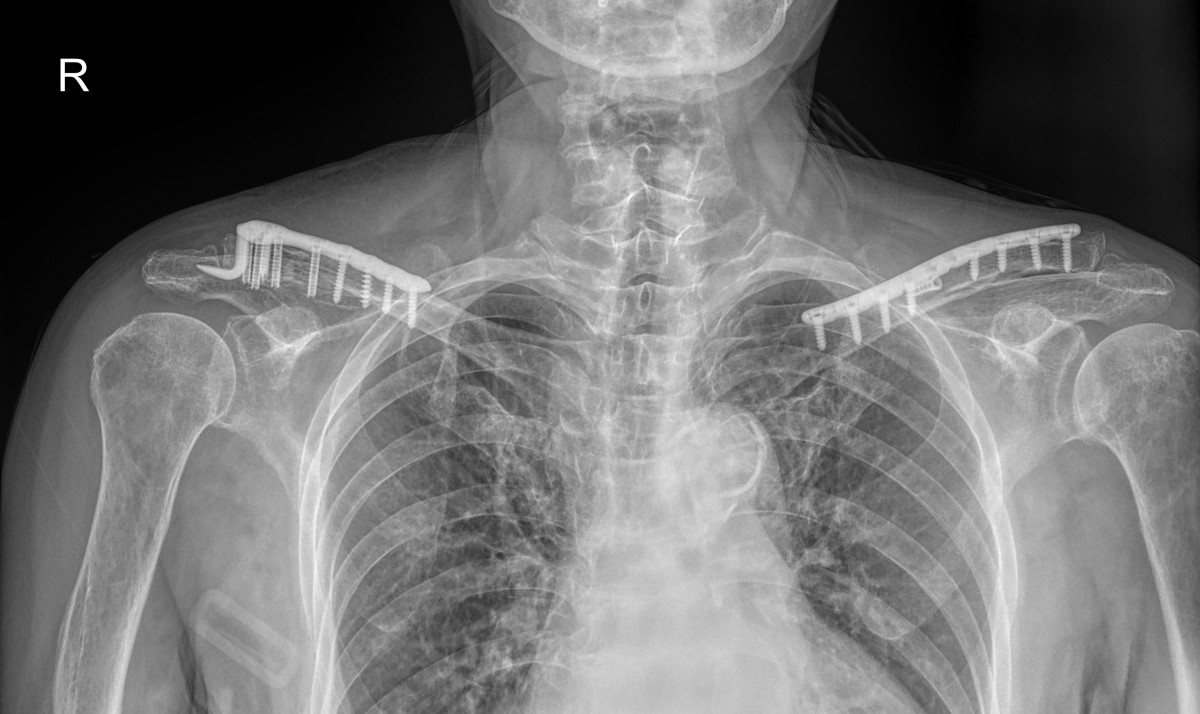

정지영원장님 어깨 골절 수술 장매O 환자

작성자 최고관리자 댓글 0건 조회 709회 작성일 25-09-16 16:40

dae765e4d9ac96aee867c9d6292d8784_1758008403_4261.jpg